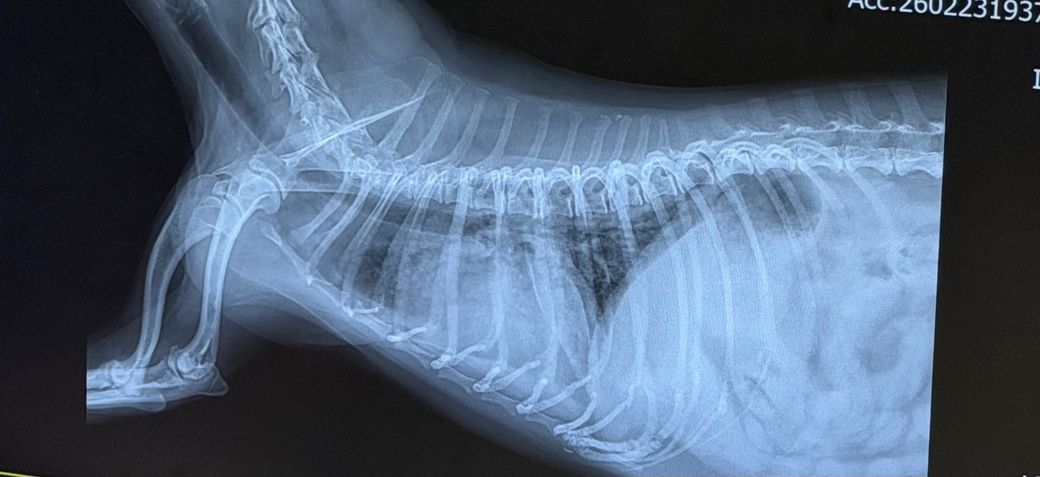

2차 병원 흉부 X-ray 결과:

복배상 폐 우측 중엽의 경화상이 관찰되는 상태이며 심장의 변위 양상이 관찰되지 않습니다.

흉수가 소량 동반되어 있으나 폐 전엽의 뒤쪽 변연의 방향, 폐 중엽의 뒤쪽 변연 주행 방향을 볼때 폐 염전으로 볼 근거는 부족하며

심장의 크기 증가 및 흉골 접합면적 증가, 좌심방 돌출 양상이 동반되며 복배상 폐후엽의 침윤 양상이 동반되어 관찰되는 상태로 심인성 폐수종을 고려해야 하는 소견입니다.

"몇 달 전부터 간헐적으로 헥헥거림이 있었고, 평소엔 비교적 잘 지내다가 흥분 시 끅끅거리는 기침이 있었"으며 이는 심장 질환의 전형적인 증상이기 때문에 우선 집중적인 심장에 대한 평가와 공격적 치료가 우선한다고 판단되니 주치의와 진솔하게 대화하고 결정하시기 바랍니다. 특히 흉수가 동반된 심인성 폐수종은 예후가 매우 불량한것으로 알려져 있습니다.